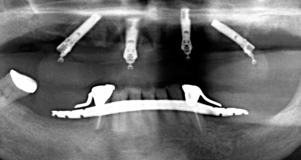

最低4本のインプラントを埋入し、それらを連結し、半日で固定式の仮歯まで入れて審美性、機能性を一日でとりもどせる革新的な治療。

1.従来インプラントは歯茎の中の骨に結合する3〜6ヶ月までは、歯をいれて噛ませることはできないと言われてきましたが、特殊な手術法によりインプラントを埋入し、4本〜6本を連結固定することにより、手術したその日からインプラントで食事を噛んでもらうことができるようになります。

3.インプラントの本数を少なくできることは、経済的も優れています。従来の治療では、無歯はでは10〜14本のインプラントを埋入していたのでそれと比較すると、かなりの治療費を削減できると考えます。